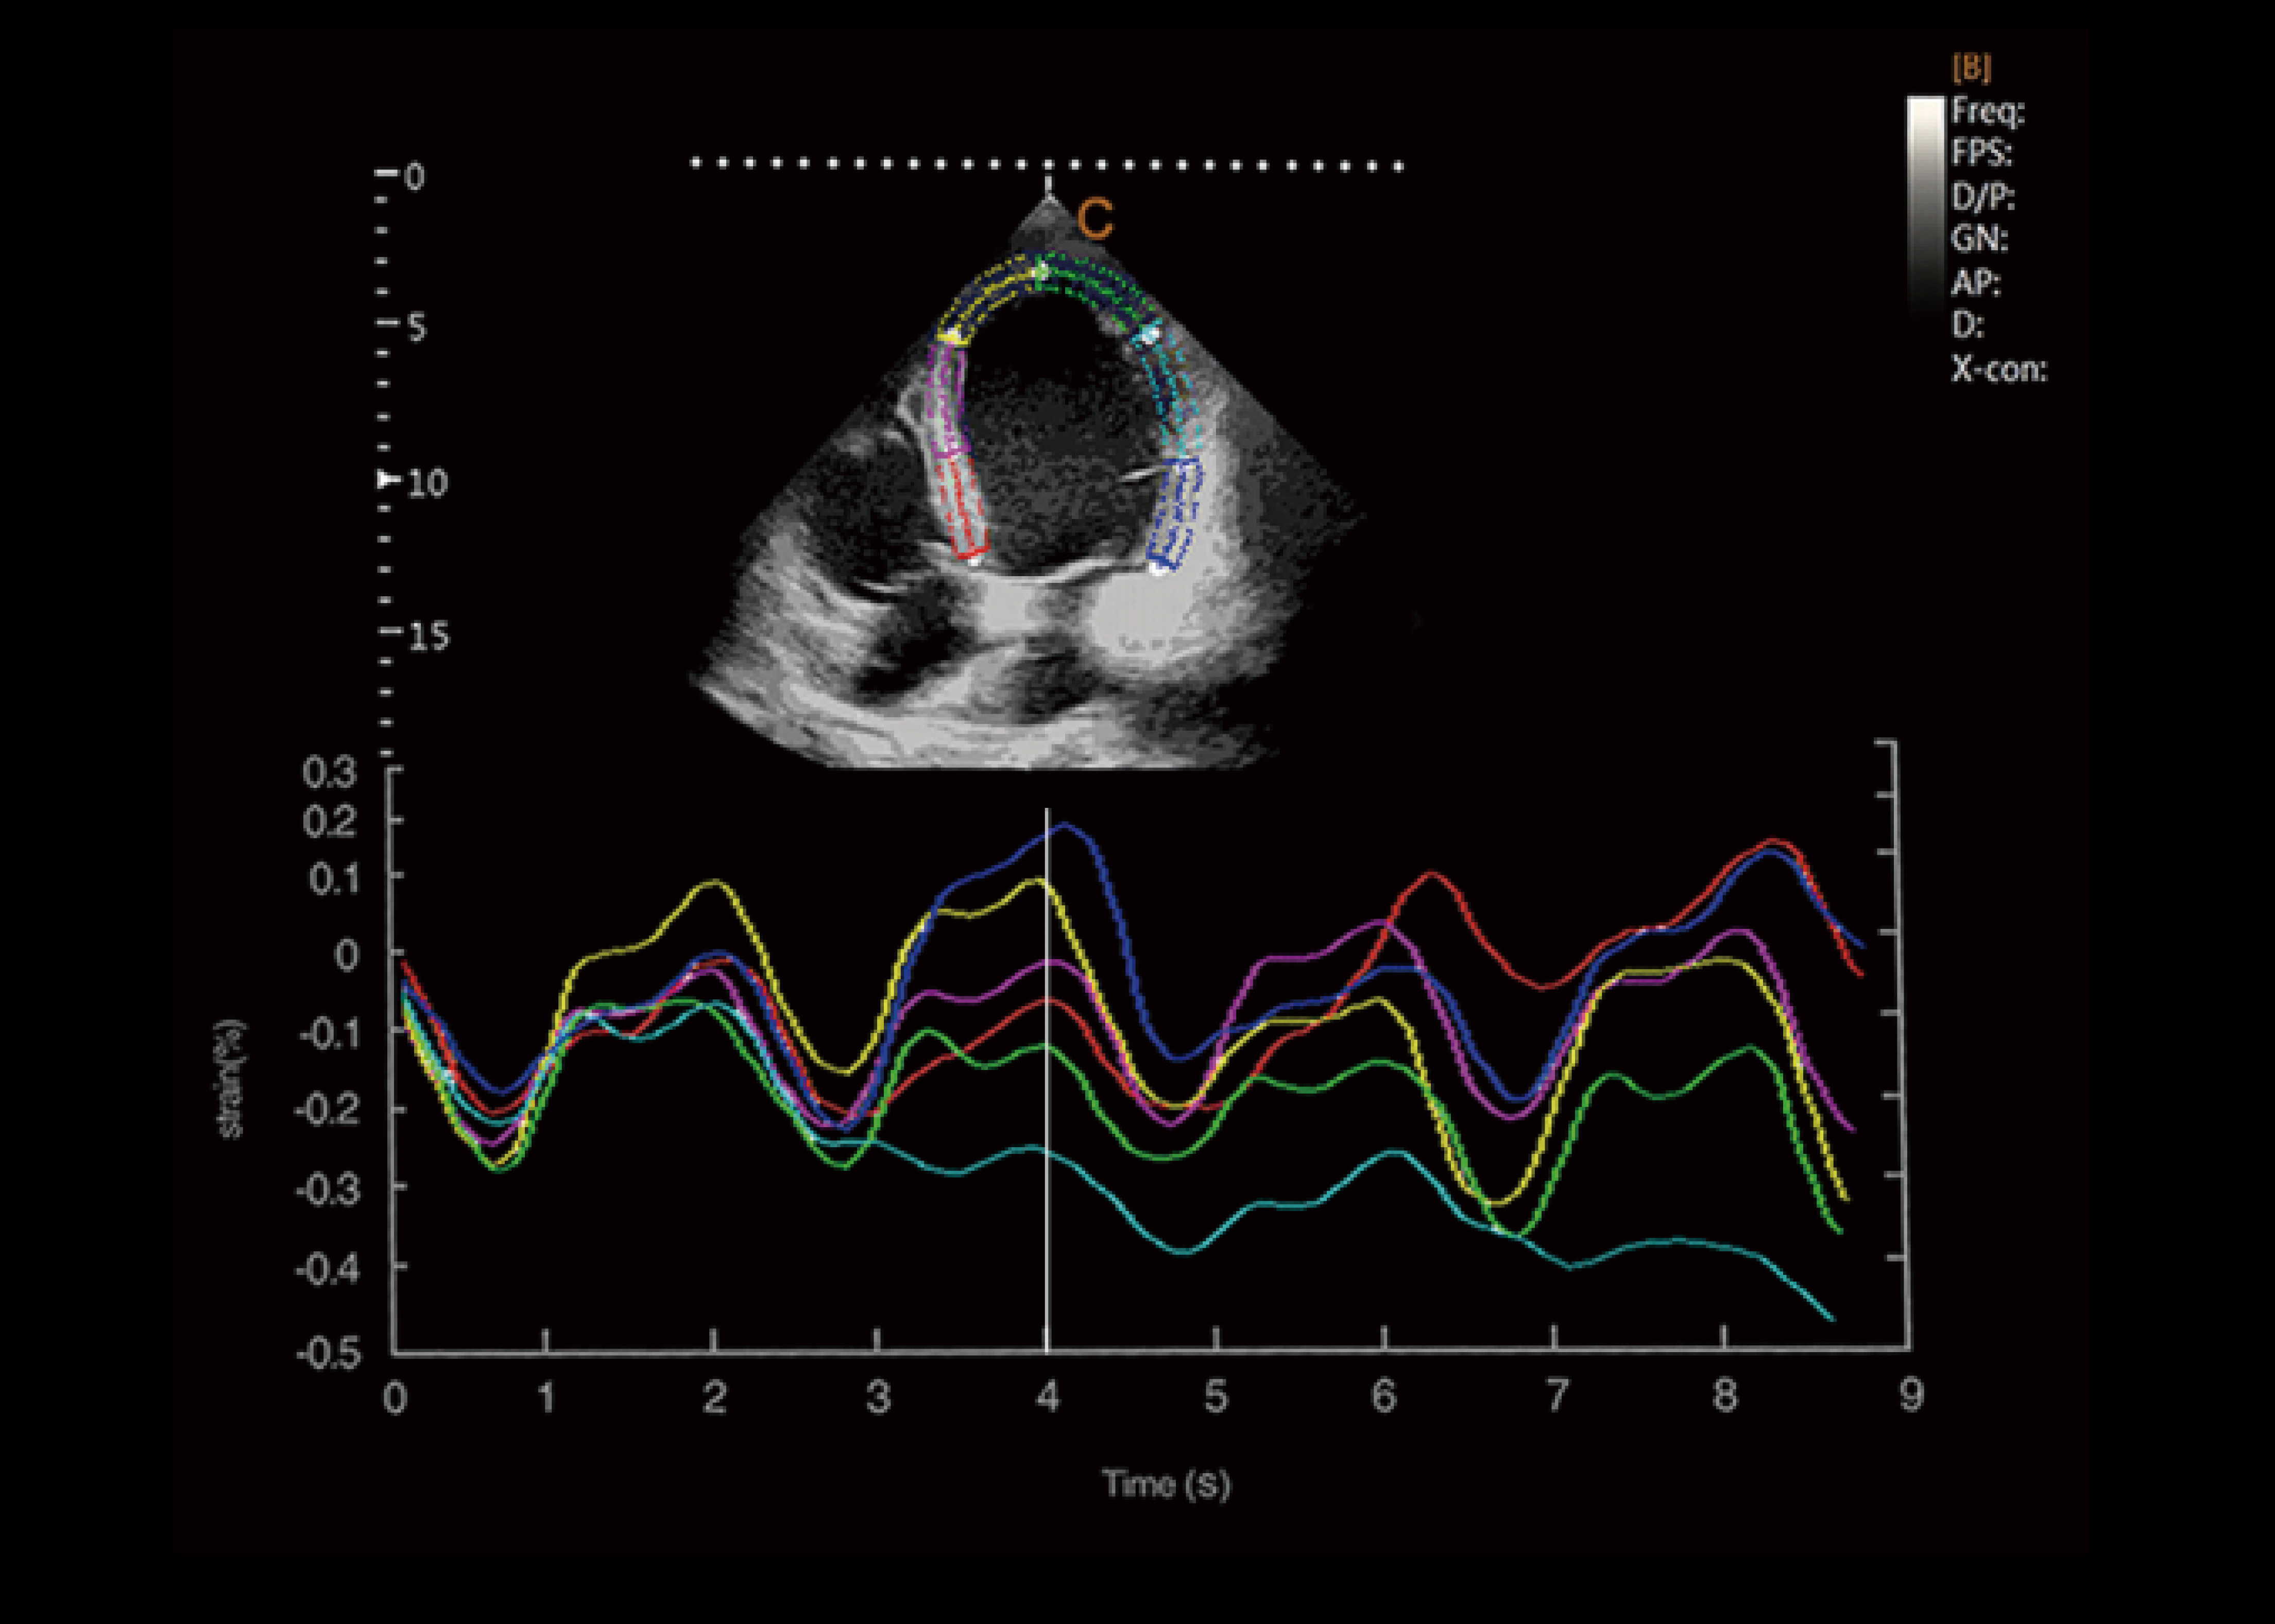

Austausch von Kardioloischen fällen / Update

Die Bedeutung der kardiologischen Untersuchung wird durch die ständig zunehmende Häufigkeit von Herzerkrankungen unterstützt. CHISON XBit 90 kann eine höhere Empfindlichkeit bieten, die für die Erkennung bestimmter Erkrankungen erforderlich ist, und hilft Ärzten, mehr Vertrauen bei der Durchführung von Herzuntersuchungen zu gewinnen.

Dehnung und Dehnungsverhältnis

● Eine neue nicht-invasive Methode zur Bewertung der Herzmuskelfunktion.

● Fähigkeit, zwischen aktiver und passiver Bewegung zu unterscheiden von Herzmuskelsegmenten, zur Quantifizierung der intraventrikulären Dyssynchronie.

● Bewertung der Komponenten der Herzmuskelfunktion.